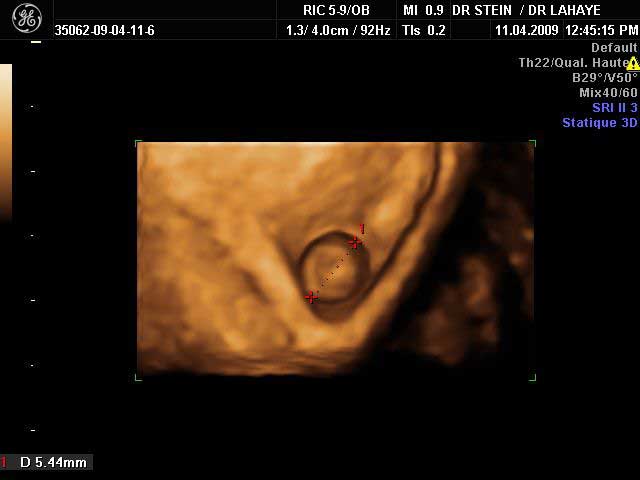

L'implantation de l'œuf

Photo echo

L'embryon se développe

Aspect échographie